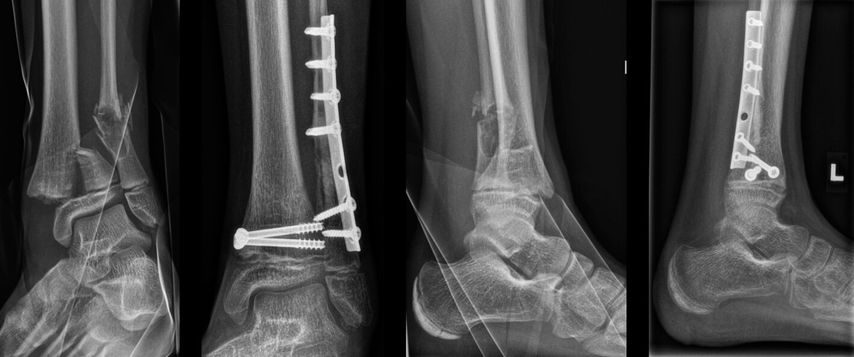

Abb. 5: 11-jähriges Mädchen mit pathologischer Fraktur der distalen Fibula bei einem nichtossifizierenden Fibrom (NOF), prä- und postoperative Röntgenaufnahme des linken Sprunggelenkes. Eine Allograft-Knochenschraube wurde als Platz- und Abstandhalter und zur biologischen Integration eingesetzt und mit Drittelrohrplatte gesichert

Ein nicht alltäglicher Einsatz einer Allograft-Knochenschraube (Shark Screw®, Surgebright GmbH) erfolgte bei einer distalen Unterschenkelfraktur einer 11-jährigen Patientin mit pathologischer Fraktur der distalen Fibula bei einem nichtossifizierenden Fibrom (NOF). Die Fraktur ereignete sich im Rahmen eines Turnunfalls. Die operative Versorgung umfasste eine offene Reposition der distalen Tibia mit Schraubenosteosynthese, danach Kürettage des fibulären NOF mit Plattenosteosynthese. Hierbei wurde die Allograft-Knochenschraube als Platz- und Abstandhalter und zur biologischen Integration eingesetzt (Abb. 5). Wird die Allograft-Knochenschraube in lebendes Knochengewebe eingesetzt, integriert sie sich in die lokale Blutversorgung, wodurch Wirtszellen in die Havers-Kanäle des Transplantats einwandern können.14 Allogene Knochenschrauben zeigen bei unterschiedlichen Indikationen vielversprechende Ergebnisse mit höheren Heilungsraten und schnellerer Konsolidierung im Vergleich zu Metallimplantaten. Dies könnte ihren Einsatz bei kindlichen Osteotomien erweitern und langfristig die Notwendigkeit von Metallentfernungen reduzieren.15